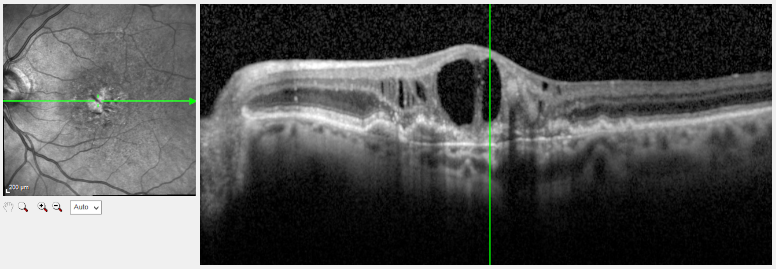

Beispiel einer feuchten Makuladegeneration in der OCT Messung mit einem genauen Querschnitt durch die Netzhaut. Man erkennt die großen schwarzen Flüssigkeits-Zysten, die hier nicht hingehören.